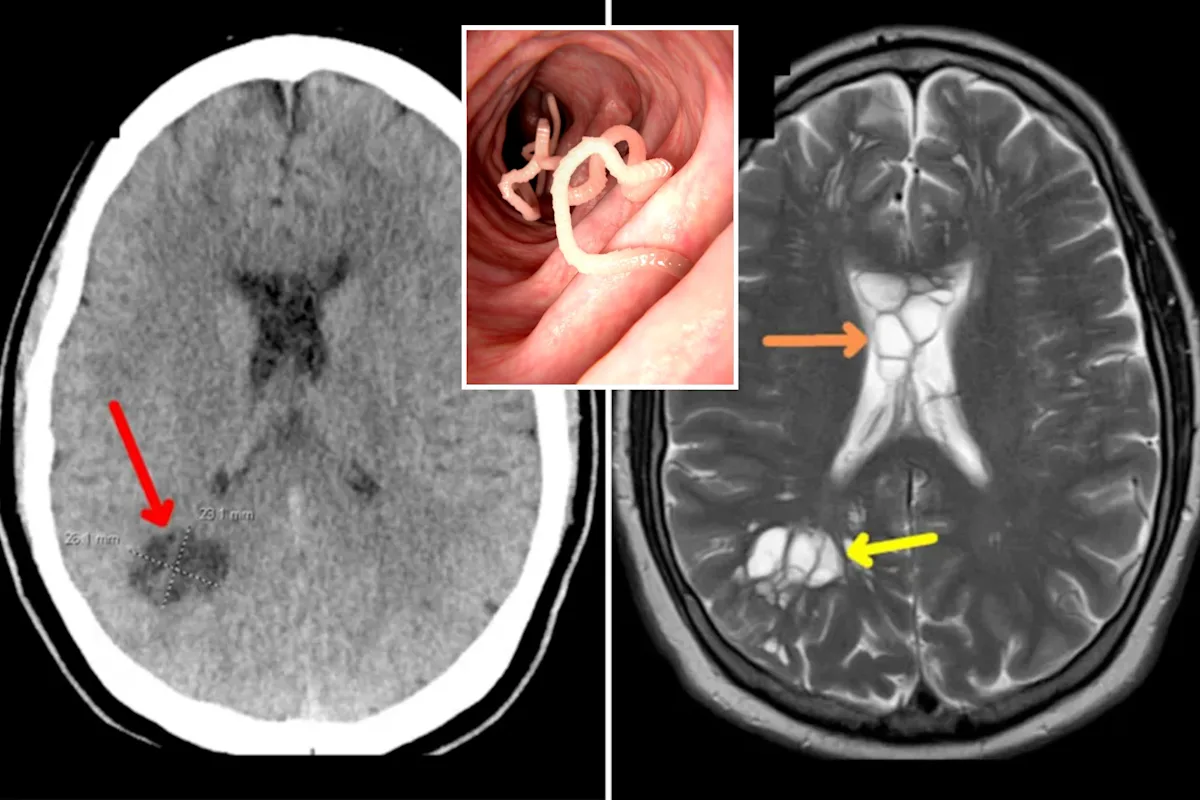

A 52-year-old American man with a history of consuming undercooked pork presented with severe migraines, leading to the discovery of tapeworm larvae in his brain. The condition, neurocysticercosis, is caused by ingesting eggs found in the feces of humans with taeniasis. The patient was successfully treated with anti-inflammatory and anti-parasitic medications after admitting to a lifelong preference for undercooked pork. The case highlights the rare but potential risk of neurocysticercosis from autoinoculation due to improper handwashing after contracting taeniasis.

A 52-year-old man in the US developed tapeworm larva in his brain, likely from consuming undercooked bacon, leading to neurocysticercosis. Despite no recent travel to endemic areas or contact with pigs, the man's habit of eating undercooked bacon and poor hand hygiene likely caused the infection. The case highlights the increasing frequency of such infections in developed countries and the importance of considering neurocysticercosis in evaluating acute changes in migraines.

A 52-year-old man in Florida suffering from chronic migraines was found to have tapeworm eggs in his brain, causing significant swelling and cysts. The parasite likely entered his body through undercooked bacon consumption, leading to a diagnosis of neurocysticercosis. Despite not having recently traveled abroad, the man's case highlights the potential risks of consuming contaminated food. He was treated with anti-inflammatory and antiparasitic medications to address the infection and swelling.

A 52-year-old man in Florida who suffered from persistent migraines was found to have a live tapeworm in his brain that had laid eggs, causing cysts and swelling. It's believed that he contracted the parasite from eating undercooked bacon. The condition, known as neurocysticercosis, can be life-threatening if left untreated. The patient was treated with medication and his cysts disappeared, leading to an improvement in his migraines. The case highlights the potential public health implications of encountering infected pork in the United States.